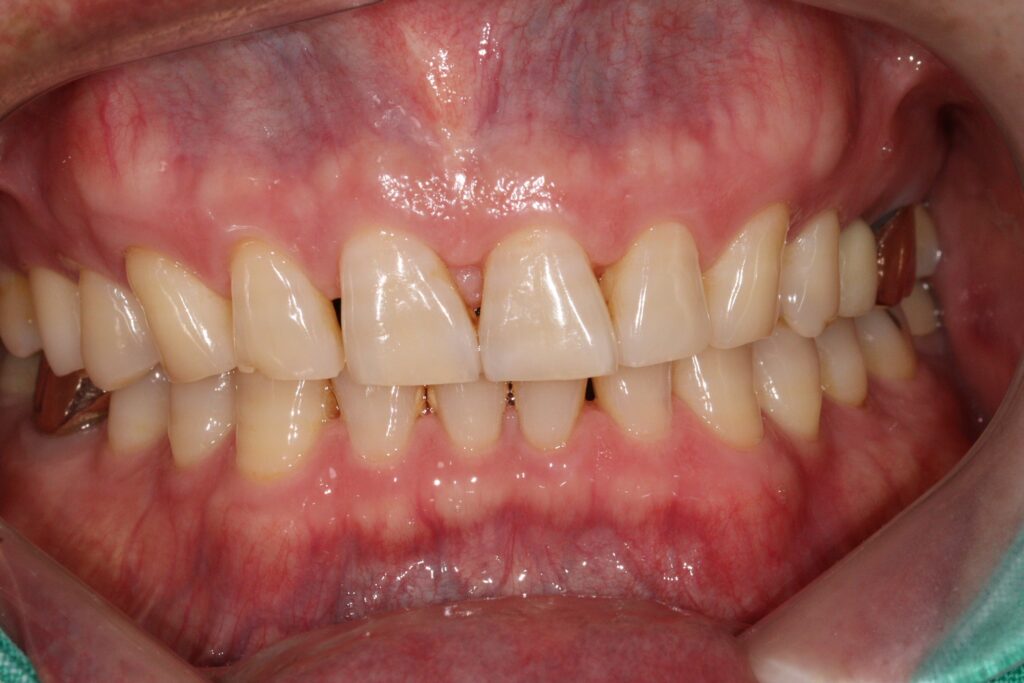

오늘은 광화문치과에서 뿌리까지 금이 간 치아를 발치한 뒤

즉시 임플란트를 식립하신 환자분을

소개해 드리도록 하겠습니다.

광화문치과 임플란트 치료는 환자마다 구강 상태가

다르기 때문에 동일한 방식으로 진행하기보다

정밀 진단을 기반으로 한 맞춤형 치료 계획이

중요하므로 임플란트 가격이나 비용뿐 아니라

치료 과정과 관리 계획까지 충분히 이해한 뒤

결정하는 것이 바람직합니다.